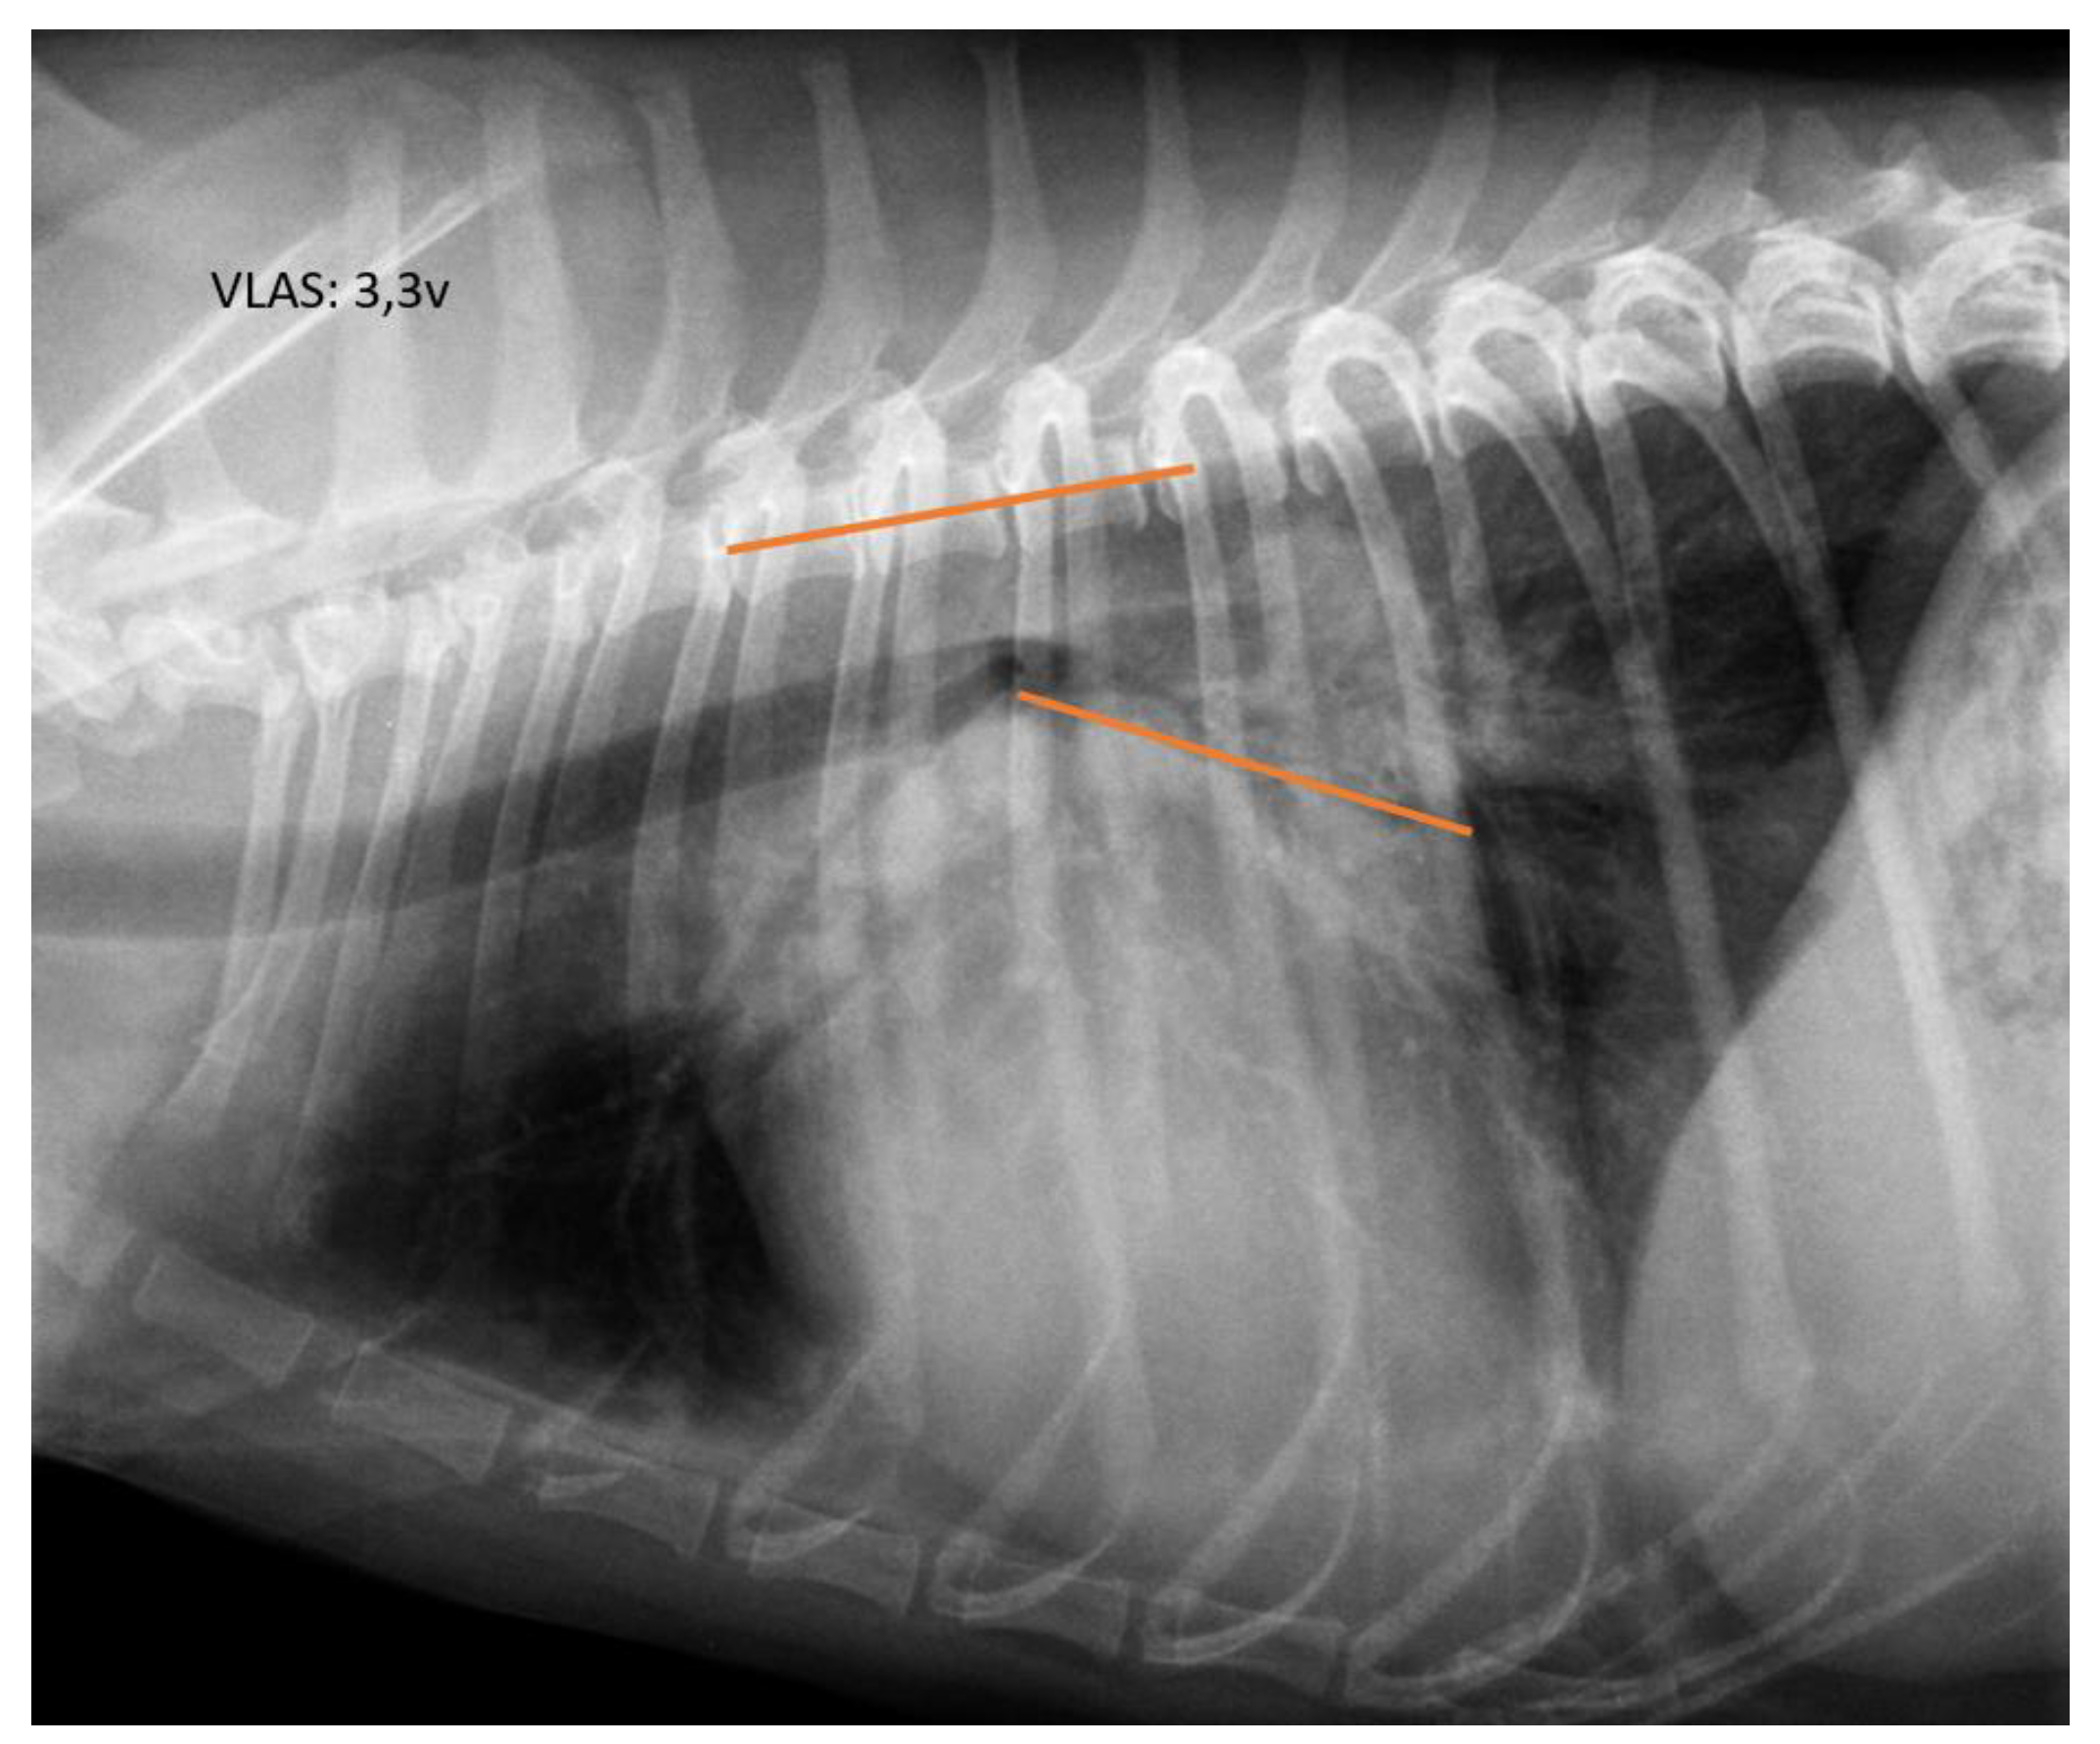

2.2. Radiographic Measurements